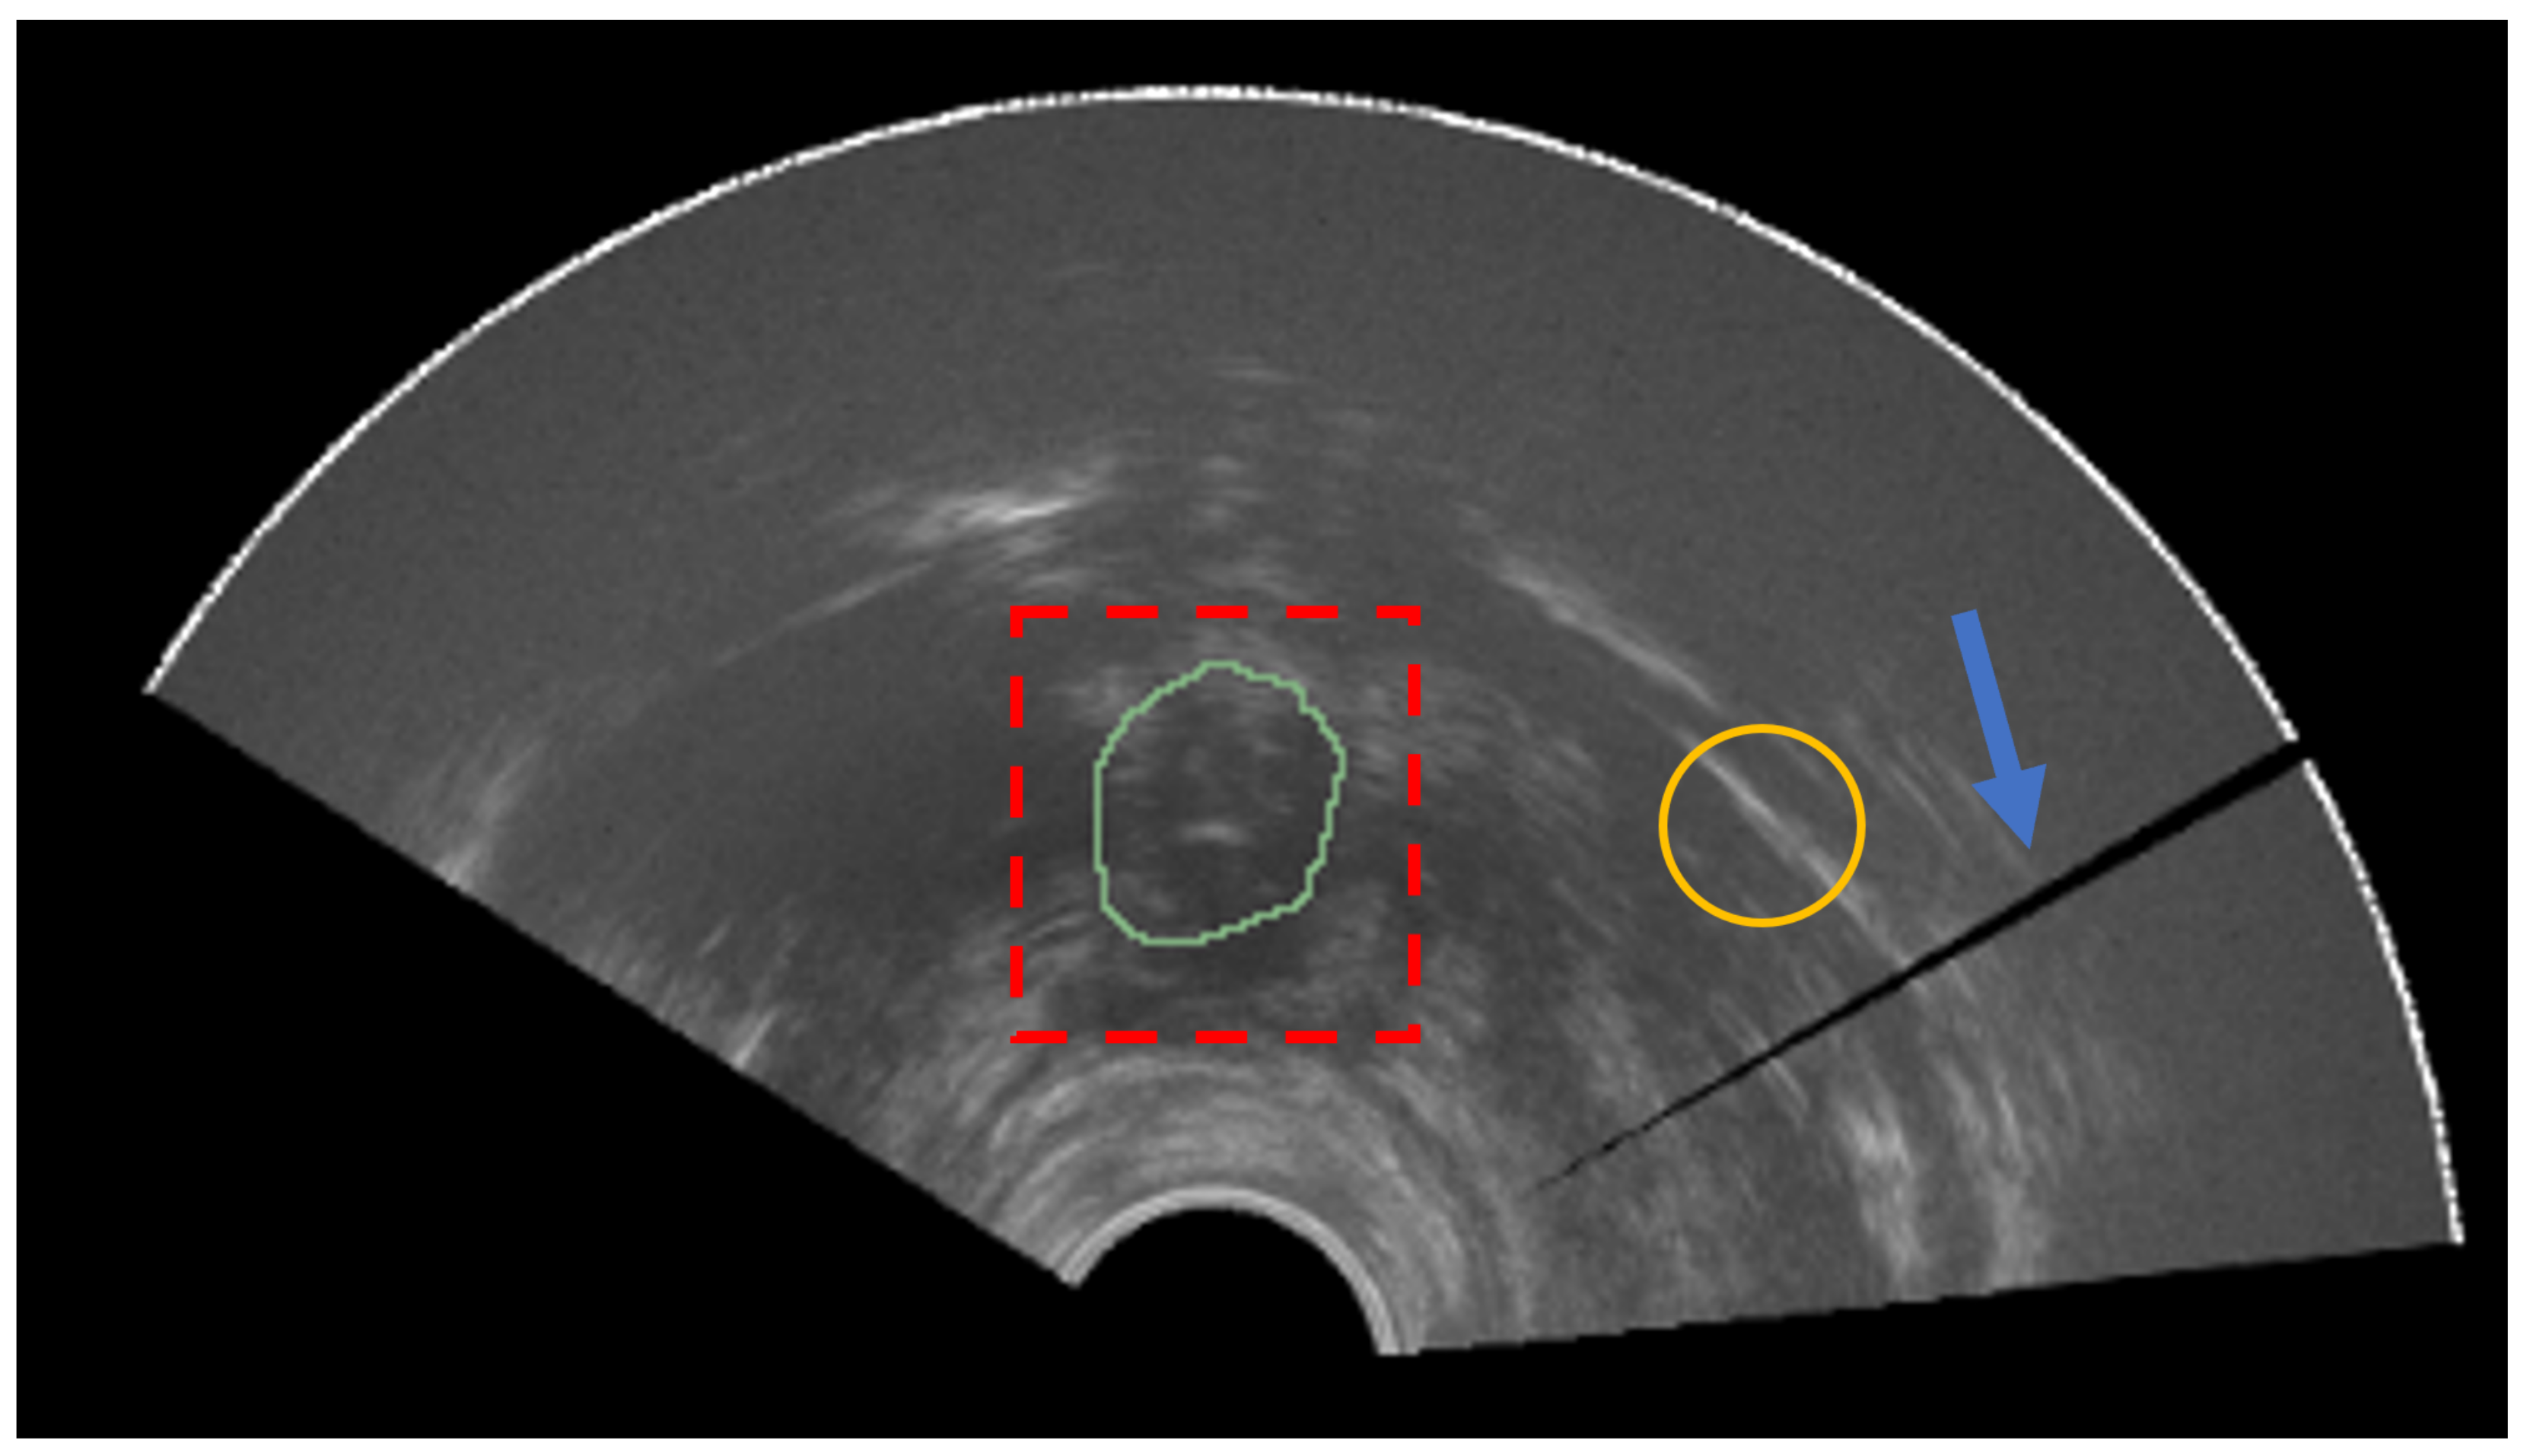

Sample images for both domains, TRUS and MRI, are reported in Figure 2. A summarized table for the considered materials is provided in Table 1.

Figure 2.

Samples of images from both modalities. (Top) Prostate MRI. From left to right, a sample image for each of the datasets—PROMISE12, SAML, and ZENODO—is shown. (Bottom) Three sample prostate TRUS from the ZENODO dataset.